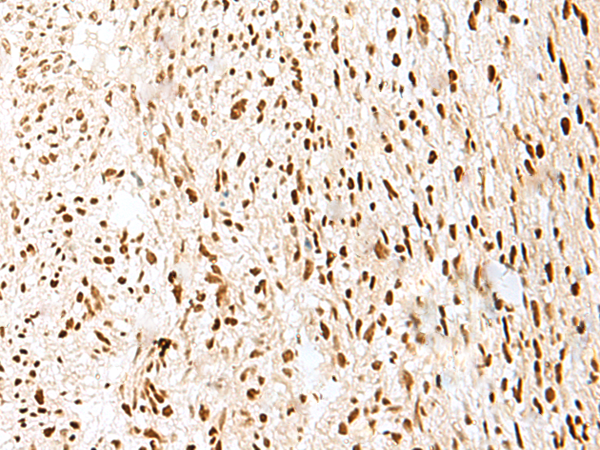

分类: 科研抗体货号: P09939别名: ASCIZ; ZNF822应用: IHC反应种属: Human, Mouse